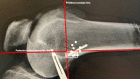

Methods: Using a pilot cadaveric specimen, the center of the radiographic safe isometric area for femoral fixation of LET, defined as a 1 cm (proximal-distal) area located proximal to the metaphyseal flare and posterior to the posterior cortical extension line (PCEL), was located using fluoroscopy and found to be 20 mm directly proximal to the center of the fibular collateral ligament (FCL) origin. Using 10 additional specimens, the center of the FCL origin and a location 20 mm directly proximal was identified. K-wires were placed at each location. A lateral radiograph was obtained, and distances of the proximal K-wire relative to the PCEL and metaphyseal flare were measured. The location of the proximal K-wire relative to the radiographic safe isometric area was assessed by 2 independent observers. Intrarater and inter-rater reliability was calculated for all measurements using intraclass coefficients (ICCs).

Results: There was excellent intrarater and inter-rater reliability for all radiographic measurements (.908 to .975 and .968 to .988, respectively). In 5/10 specimens, the proximal K-wire was outside of the radiographic safe isometric area, with 4/5 anterior to the PCEL. Overall, the mean distance from the PCEL was 1 mm ± 4 mm (anterior), and the mean distance from the metaphyseal flare was 7.4 mm ± 2.9 mm (proximal).